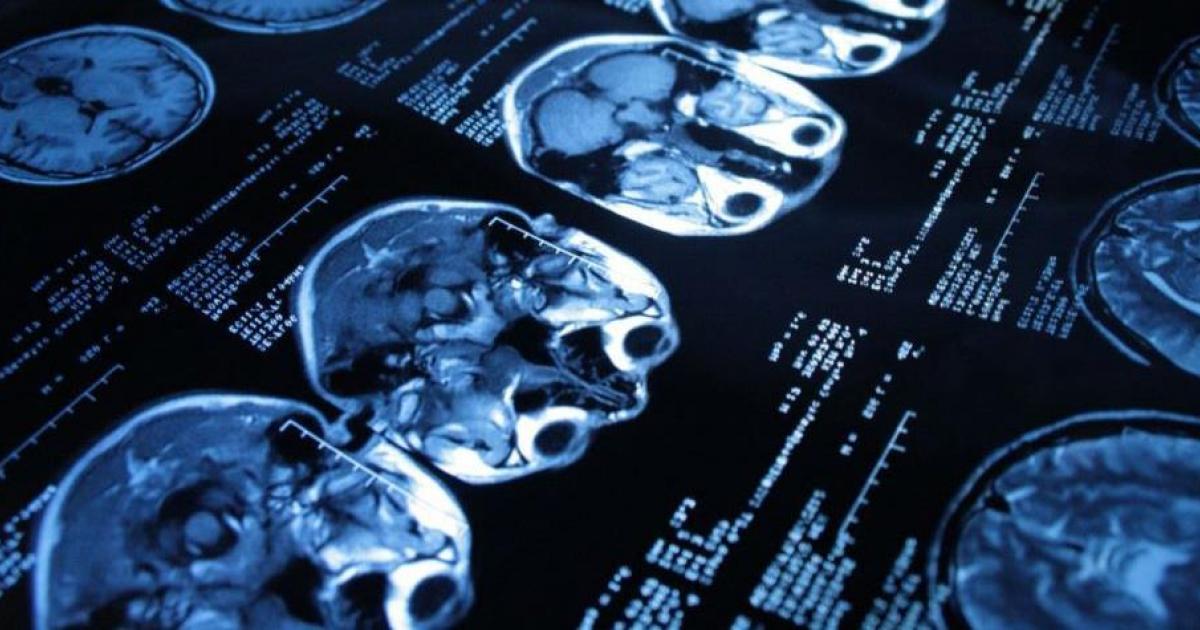

Быстрое обнаружение с точной сегментацией очага очень важно для оказания помощи пациентам с инсультом при использовании эндоваскулярной хирургии. Чаще всего сегментация очага определяется вручную специалистами, что может приводить к недостаточно точному диагнозу.

Исследование, опубликованное в журнале Neuroscience Methods, предлагает новый автоматизированный метод обнаружения и сегментации очага по снимкам МРТ.

Для нового метода используется сравнение диффузионной спектральной томографии пациента и снимков группы здоровых людей на пиксельном уровне. Области с гиперинтенсивностью идентифицируются и маркируются как очаги поражения. Метод был исследован в рамках 200 снимков МРТ.

Полученные результаты демонстрируют, что он может дополнять работу специалиста-радиолога. При этом сам процесс не требует оборудования с высокой мощностью.